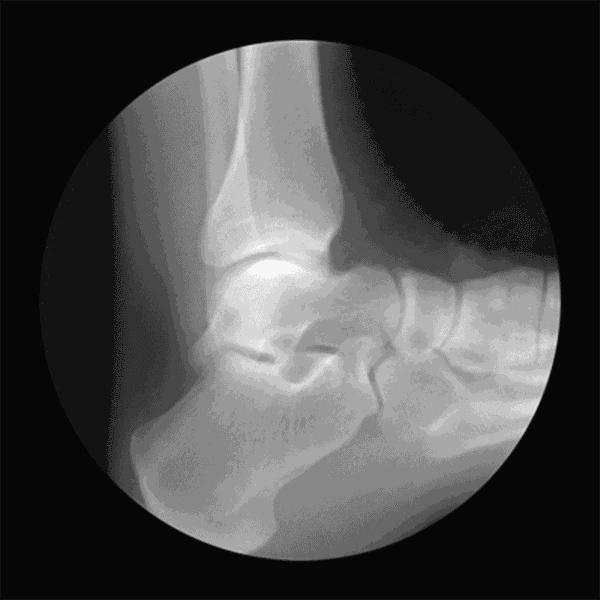

与之对应的是,骨刺主要长在负重大、使用频繁的关节部位,如颈椎、腰椎、膝盖、脚跟等,这从另一面验证了上述理论。

举个例子,足跟部骨刺早期确实非常疼痛,但是,一旦足跟部重新获得稳定,疼痛会好转或自行消除,可见人体是多么奇妙。